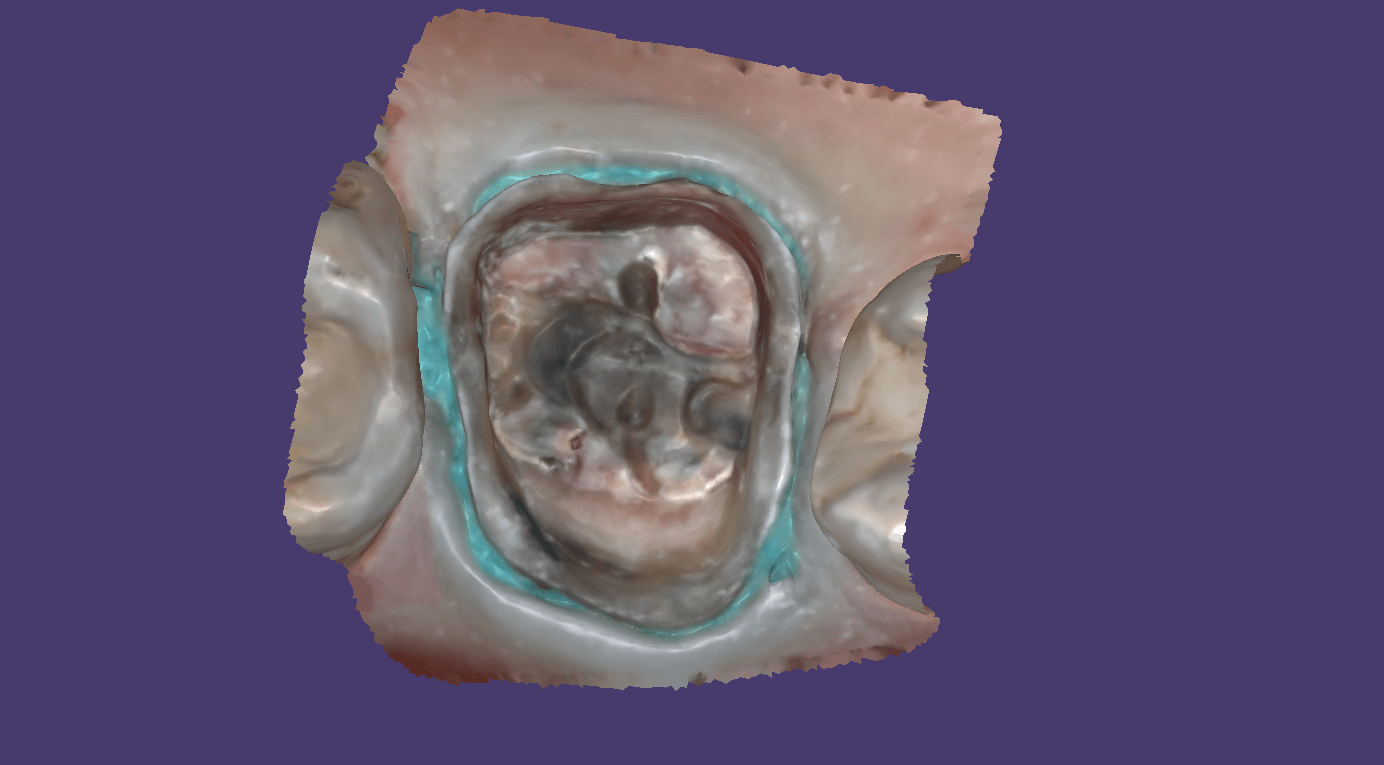

You can then take the prosthesis out of the mouth and continue imaging it and roll over to the intaglio and capture that information.

You can even reline the prosthesis to get the best adaptation possible, scan that, clone the case, and then use the edit tool to crop out everything but the intaglio. What remains is the edentulous ridge that is properly mounted to the opposing arch where you can start designing the desired final restoration.